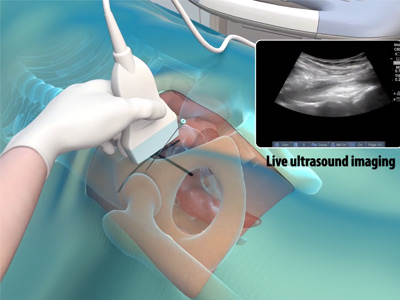

Platelet Rich Plasma (PRP) Injections for the Hip Ultrasound Guided Hip Injections

Ultrasound Guided Hip Injections